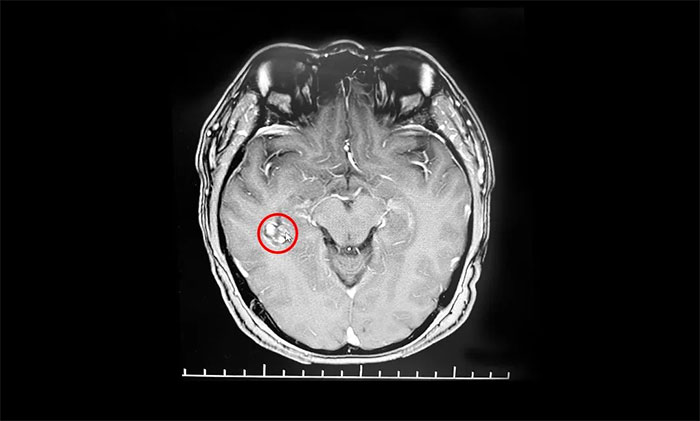

入院后,行海马MRI平扫+MRS+MRSI检查,MRS提示右侧海马Cho峰升高;扫及右侧颞叶深部(侧脑室颞角外下部)见一直径约15mm类圆形异常信号;右侧侧脑室颞角稍宽。患者既往高血压病史4年,曾因右侧颞部海绵状血管瘤致蛛网膜下腔出血2次。杨忠旭教授结合患者症状,病史,磁共振、脑电图等系列检查,考虑海绵状血管瘤及周围皮层为致癫灶。患者已经明确有反复出血史,手术指征明显,需行手术切除治疗,预防再次出血引起神经功能及癫痫等症状。

▲ 海绵状血管瘤